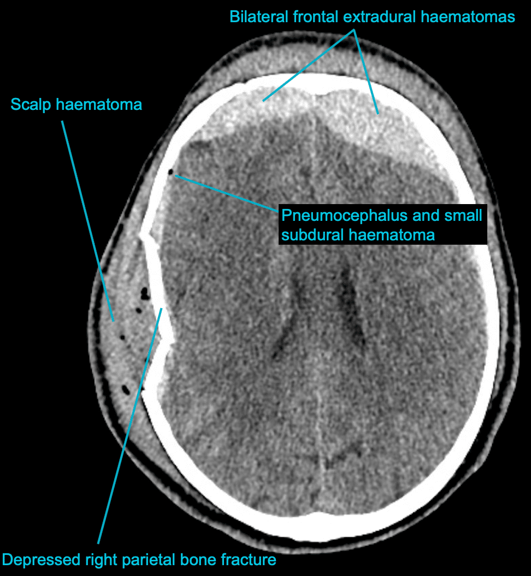

CASE 2 -A 54-year-old man walks into emergency 3 hours after a 150kg plank of wood fell on his head. He has obvious external signs of head injury and a cracking headache, however, neurologically he is intact. A CT head scan is performed

EXPLANATION –There is a depressed right parietal bone fracture with underlying pneumocephalus (indicates an open skull fracture) and a small subdural hematoma.

- Overlying this there is a scalp hematoma.

- There is also a non-displaced fracture in the frontal bone. This fracture crosses the midline and probably has injured the anterior aspect of the superior sagittal sinus.

- Tears of the dural venous sinuses may cause an extradural hematoma (EDH), as in this case. The hematoma is seen external to the compressed superior sagittal sinus.

Extradural bleeds (EDH) are located between the outer layer of dura and endosteal layer of skull. Like in this case, they are usually associated with calvarial fractures.

- They typically demonstrate biconvex or lentiform shape and are limited by sutures as periosteum is attached at the sutures limiting spread of the bleed.

- The source of bleed is arterial in origin, from a middle meningeal artery as opposed to venous in subdural bleeds.

- Up to 10% of EDH are due to venous bleeding, follow the laceration of a dural venous sinus, as we see in this case.

- There is often displacement of the sinus away from the underlying bone. There are three locations characteristic of venous EDH; the vertex, anterior middle cranial fossa and the occipital posterior fossa.

- Hypodense areas within a bleed likely represent unclotted blood suggesting active bleeding.

- As these bleeds are venous, there is not the same urgency for decompression in theatre. In fact, this patient was managed conservatively as operative intervention poses a risk of further damage to the venous sinuses.